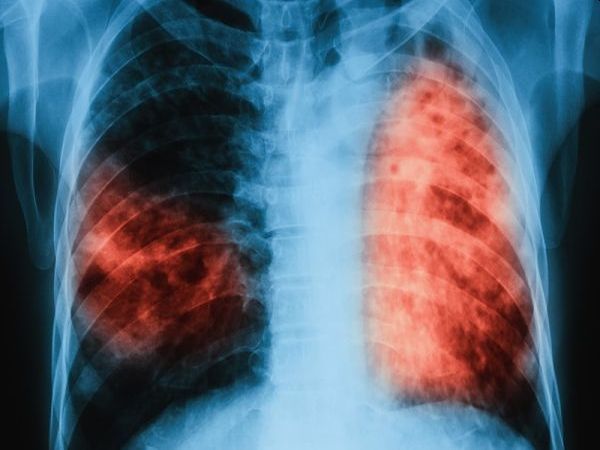

За пореден път международната общност отбеляза Световния ден за борба

... с мултирезистентна туберкулоза (MDR-TB) в СБАЛББ - Габрово. Туберкулозата е лечима и предотвратима, стига да бъде открита навреме и да бъде проведено качествено лечение, припомнят експертите.

В България e налице тенденция за трайно намаляване на заболеваемостта

Налице е тенденция за трайно намаляване на заболяемостта от туберкулоза

... заболяването, а 70 000 са лицата с мултирезистентна туберкулоза.Туберкулозата е лечима, стига да бъде открита навреме и да бъде проведено качествено лечение, допълват от Министерството.